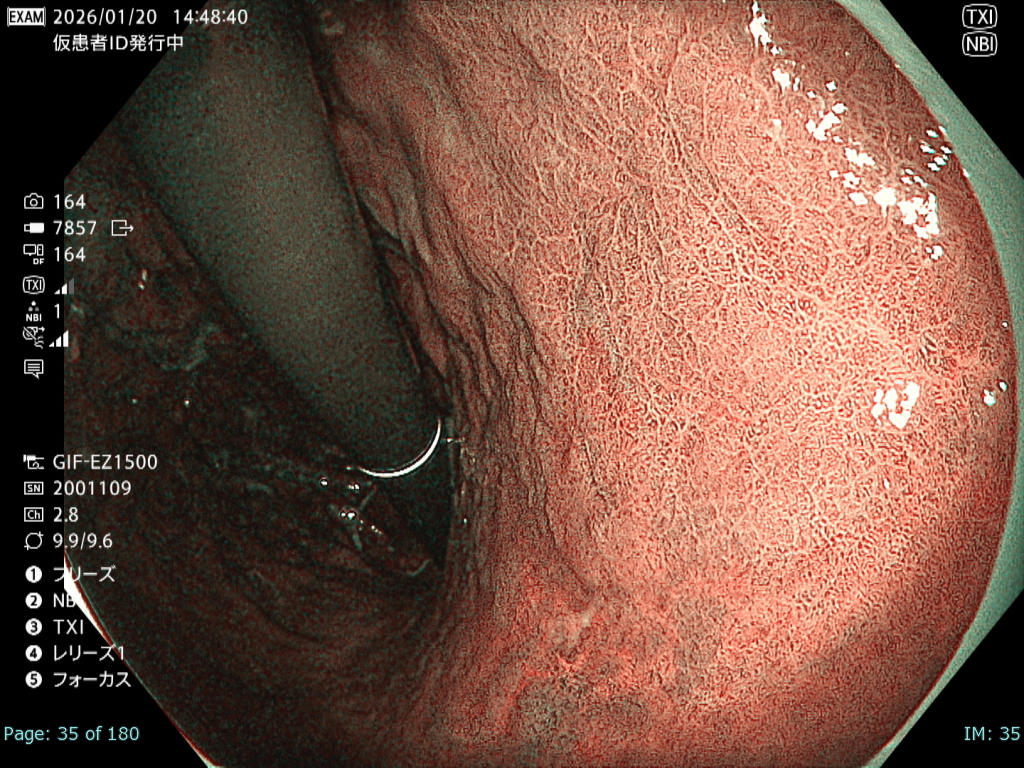

• NBI観察①(中遠景)

強調設定:B8

図3

観察中に出血が増加し、頻回の洗浄が必要となった。さらに胃管症例であったことから咳嗽が出現し、霧が生じるなど観察条件は不良であった。

• NBI+TXI観察① (中遠景)

切替前 NBI強調設定:B8

NBI+TXIレベル:中

図4

前述のとおり厳しい状況下でも、NBI+TXI観察モードは、NBI観察と比較して病変をよりシャープに描出出来ると感じた。